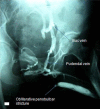

Retrograde urethrogram is employed for adequate demonstration of anterior urethral stricture and is commonly performed by trainee residents. Not uncommonly, contrast is injected under pressure to overcome the resistance of a stricture which can lead to extravasation or intravasation exposing the patient to risk of bacteremia, sepsis, contrast reactions, and worsening of stricture. We report two such cases of extensive intravasation delineating the "venogram" of peno-pelvic venous arcade. Such rare occurrences highlight the importance of eliciting history of various allergies and asthma, urethral instrumentation, obtaining sterile urine before the study, and performing the study under dynamic fluoroscopy.